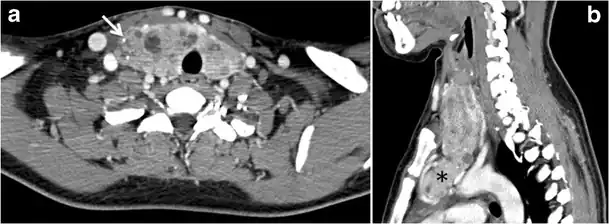

Malignancy can coexist within the goiter and a CT scan may give a clue if there are abnormal cervical lymph nodes and/or signs of invasion. Retrosternal extension (Fig. 15) could affect the surgical approach, as a lower extent may require a partial or total sternotomy to facilitate complete resection. Therefore, the distance of the retrosternal extent from the sternal notch should be measured on a sagittal image.[1]